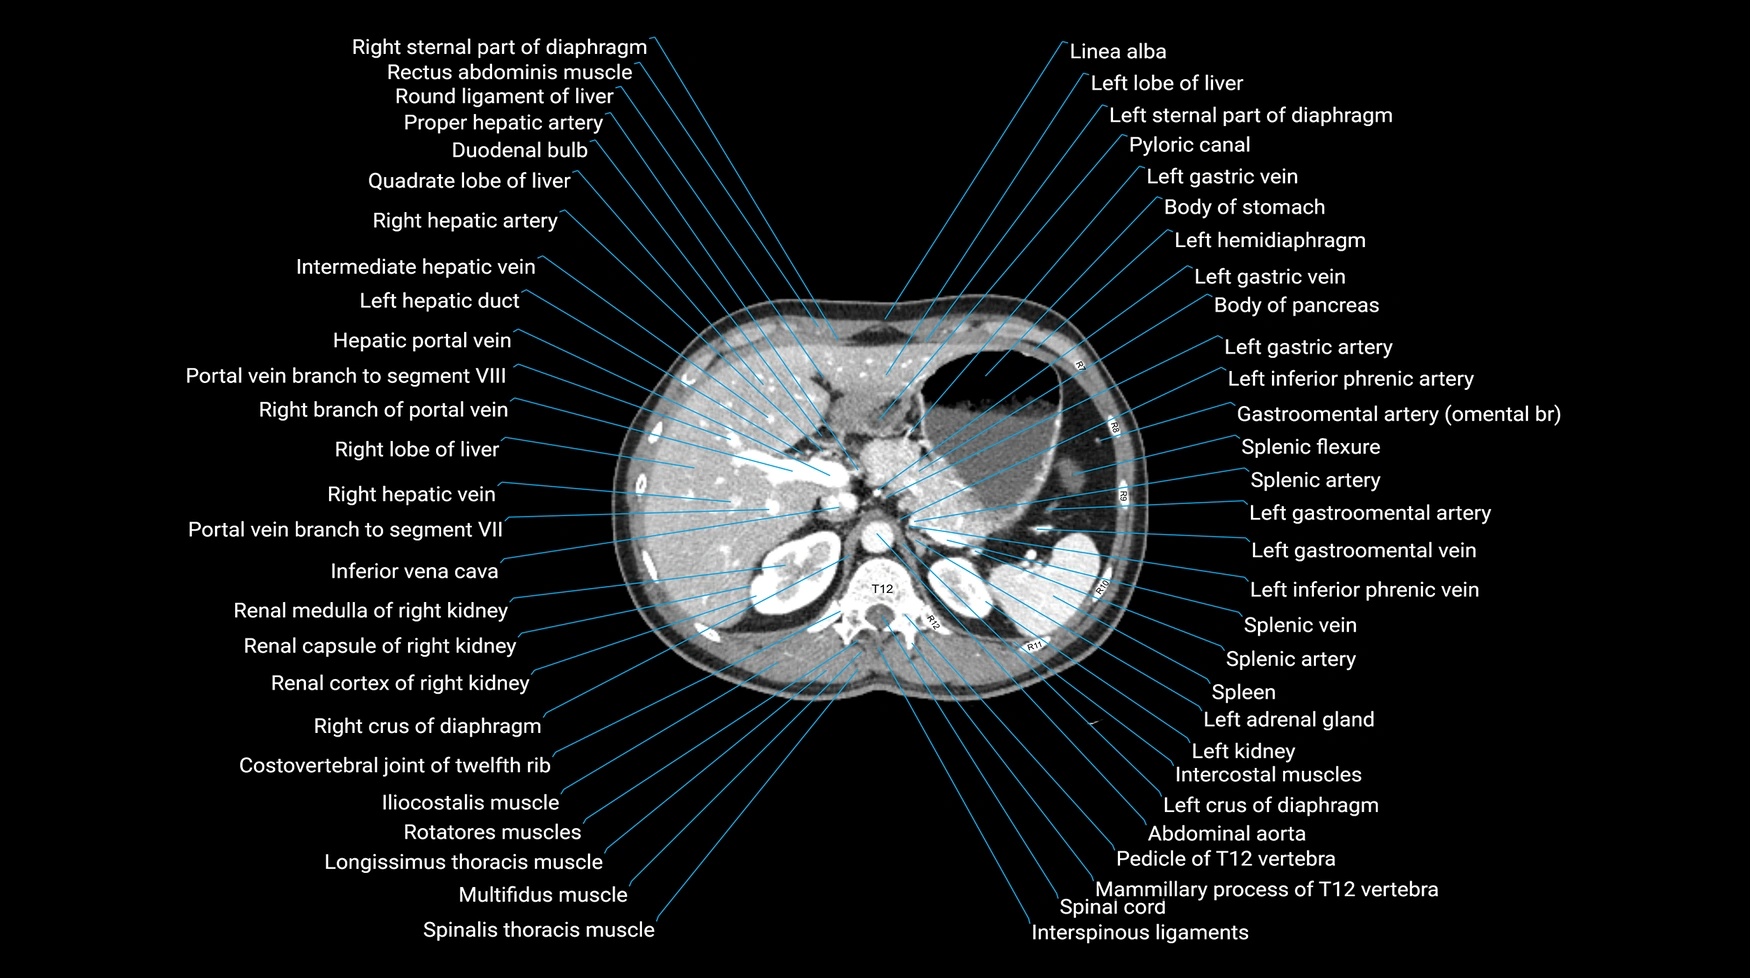

Our platform also features 1 mm high-resolution CT scans in three anatomical planes, detailed labeled anatomy, and an extensive X-ray anatomy collection. Each anatomical region is paired with dynamic quizzes that create new questions every session, helping you build lasting anatomical knowledge through active learning.

All our cross-sectional images are meticulously hand-labeled by professionals with over 20 years of experience in cross-sectional imaging. This is the result of over six years of dedicated work, precision, and passion. Every image is individually checked and verified by senior consultant radiologists from major London NHS trusts, each with relevant subspecialty expertise—ensuring the highest level of accuracy and clinical relevance.